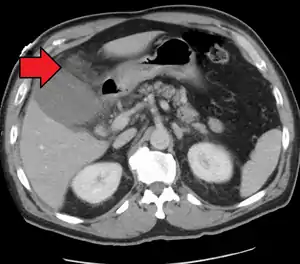

Right upper quadrant abdominal ultrasound is most commonly used to diagnose cholecystitis.[1][25][26] Ultrasound findings suggestive of acute cholecystitis include gallstones, pericholecystic fluid (fluid surrounding the gallbladder), gallbladder wall thickening (wall thickness over 3 mm),[27] dilation of the bile duct, and sonographic Murphy's sign.[13] Given its higher sensitivity, hepatic iminodiacetic acid (HIDA) scan can be used if ultrasound is not diagnostic.[13][14] CT scan may also be used if complications such as perforation or gangrene are suspected.[14]

Acute cholecystitis with gallbladder wall thickening, a large gallstone, and a large gallbladder- Significant gallbladder wall thickening[28]

- Significant gallbladder wall thickening[28]